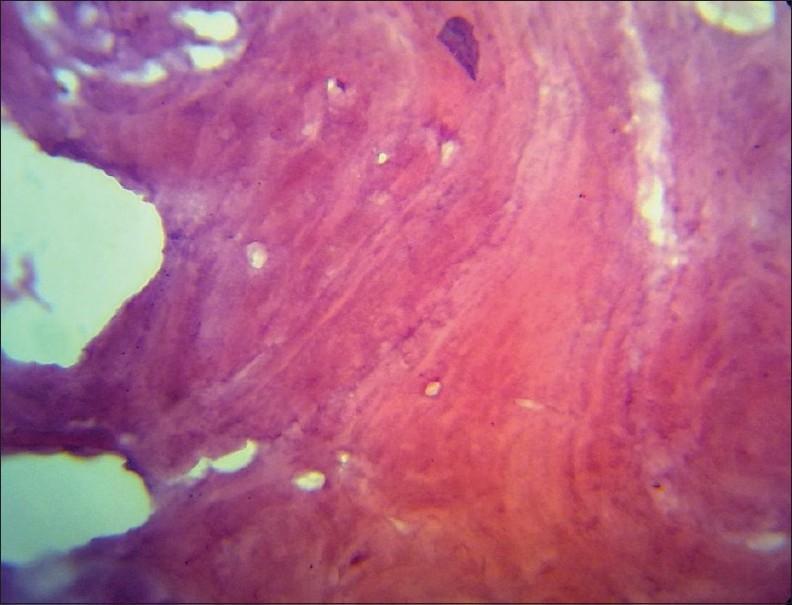

Benign cementoblastoma is a rare odontogenic tumor characterized by the formation of a mass of cementum or cementum-like tissue attached to the roots of a tooth. Cementoblastoma are distinctive but relatively uncommon tumors. The clinical, radiographic, and histopathologic features of a case of benign cementoblastoma are presented in this paper along with a brief review of the literature.

良性成牙骨质细胞瘤是一种罕见的牙源性肿瘤,其特征是形成一团附着于牙根的牙骨质或牙骨质样组织。成牙骨质细胞瘤是独特但相对不常见的肿瘤。本文介绍了一例良性成牙骨质细胞瘤的临床、影像学和组织病理学特征,并对相关文献进行了简要综述。